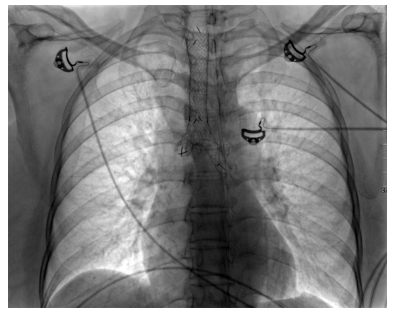

In January 2017, she presented with two- week history of worsening of shortness of breath, wheeze and stridor. Further evaluation showed interval increase in circumferential thickening of trachea and bilateral main stem and lobar bronchi on HRCT of the chest and neck. However, repeat ANCA was negative for both proteinase 3 and MPO by line immunoassay and by indirect immunofluorescence for cytoplasmic and peri-nuclear ANCA. After initial treatment with broad-spectrum antibiotics and increased steroid dose, she had a marginal improvement. Considering this as a disease relapse, she was given rituximab 2 g two weeks apart. At subsequent follow-ups, the patient was doing well with just oral prednisolone 5 mg daily. At fourth month follow-up, HRCT of the chest with neck cuts was repeated and it showed reduction in wall thickening as compared to the previous scans (Figure 2). This time, the patient was given early rituximab 500 mg maintenance therapy and discharged on same dose of oral prednisolone and cotrimoxazole.